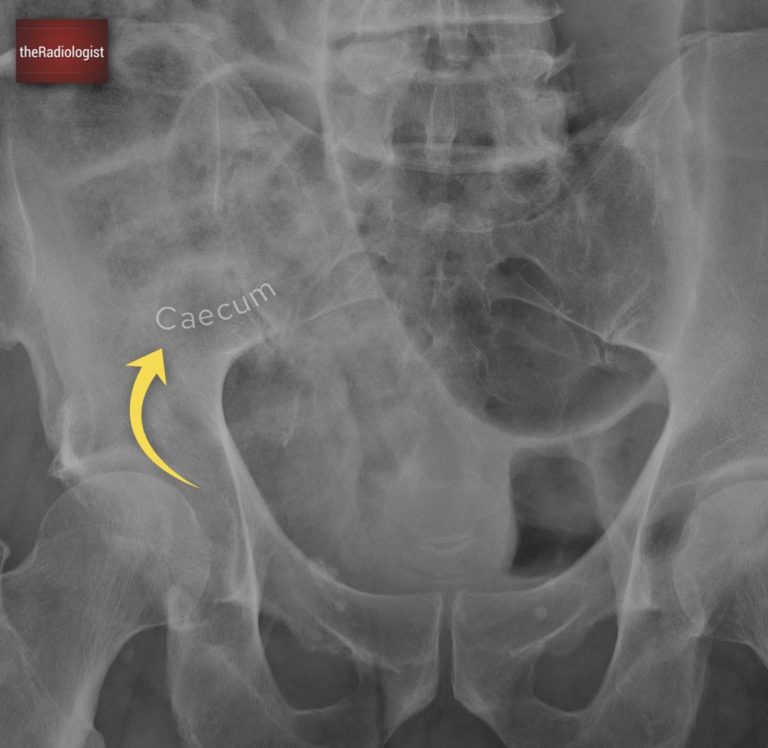

Looking at the second X-ray, there’s a crucial observation: a normal gas pattern within the ascending colon and caecum. This finding is significant because it points us toward sigmoid volvulus – if this was caecal volvulus we wouldn’t be seeing a normal gas pattern within the caecum.

We can see an expected gas pattern within the caecum within the right iliac fossa. If this was caecal volvulus we would not expect to see a normal gas pattern here making sigmoid volvulus more likely.